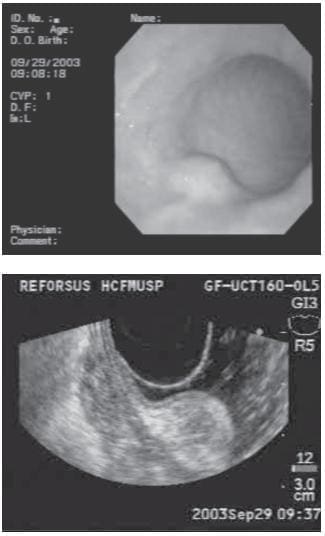

FIGURA 8. En la imagen de la izquierda se observa una lesión subepitelial gástrica y en la de la derecha, una lesión hiperecoica que depende de la tercera capa, sugestiva de un lipoma. Este ejemplo demuestra que con el equipo lineal también se pueden hacer exámenes diagnósticos.

Lesiones hiperecogénicas. La lesión que más frecuentemente se encuentra es el lipoma, el cual se caracteriza por ser hiperecogénico, homogéneo y usualmente tiene el llamado signo de la almohada a la endoscopia (figura 8). Otras lesiones hiperecogénicas que se pueden encontrar en esta capa son: adenoma de las glándulas de Brunner, linfoma gástrico, fibromas granulomas y metástasis.